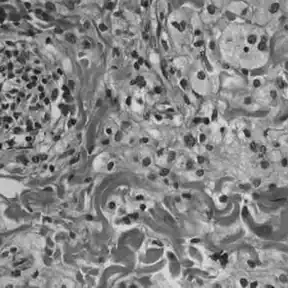

A doença de Erdheim-Chester (também conhecida como síndrome de Erdheim-Chester ou histiocitose esclerosante poliostótica) é uma forma rara de histiocitose de células que não de Langerhans. Acontece por depósito de lipídios e se enquadra no grupo das xantogranulomatoses lipídeas que incluem: granuloma necrobiótico, histiocitose de Langerhans e síndrome de Rosai Dorfman. Pode matar o paciente em 1 dia, se o primeiro sintoma for hemorragia anal.